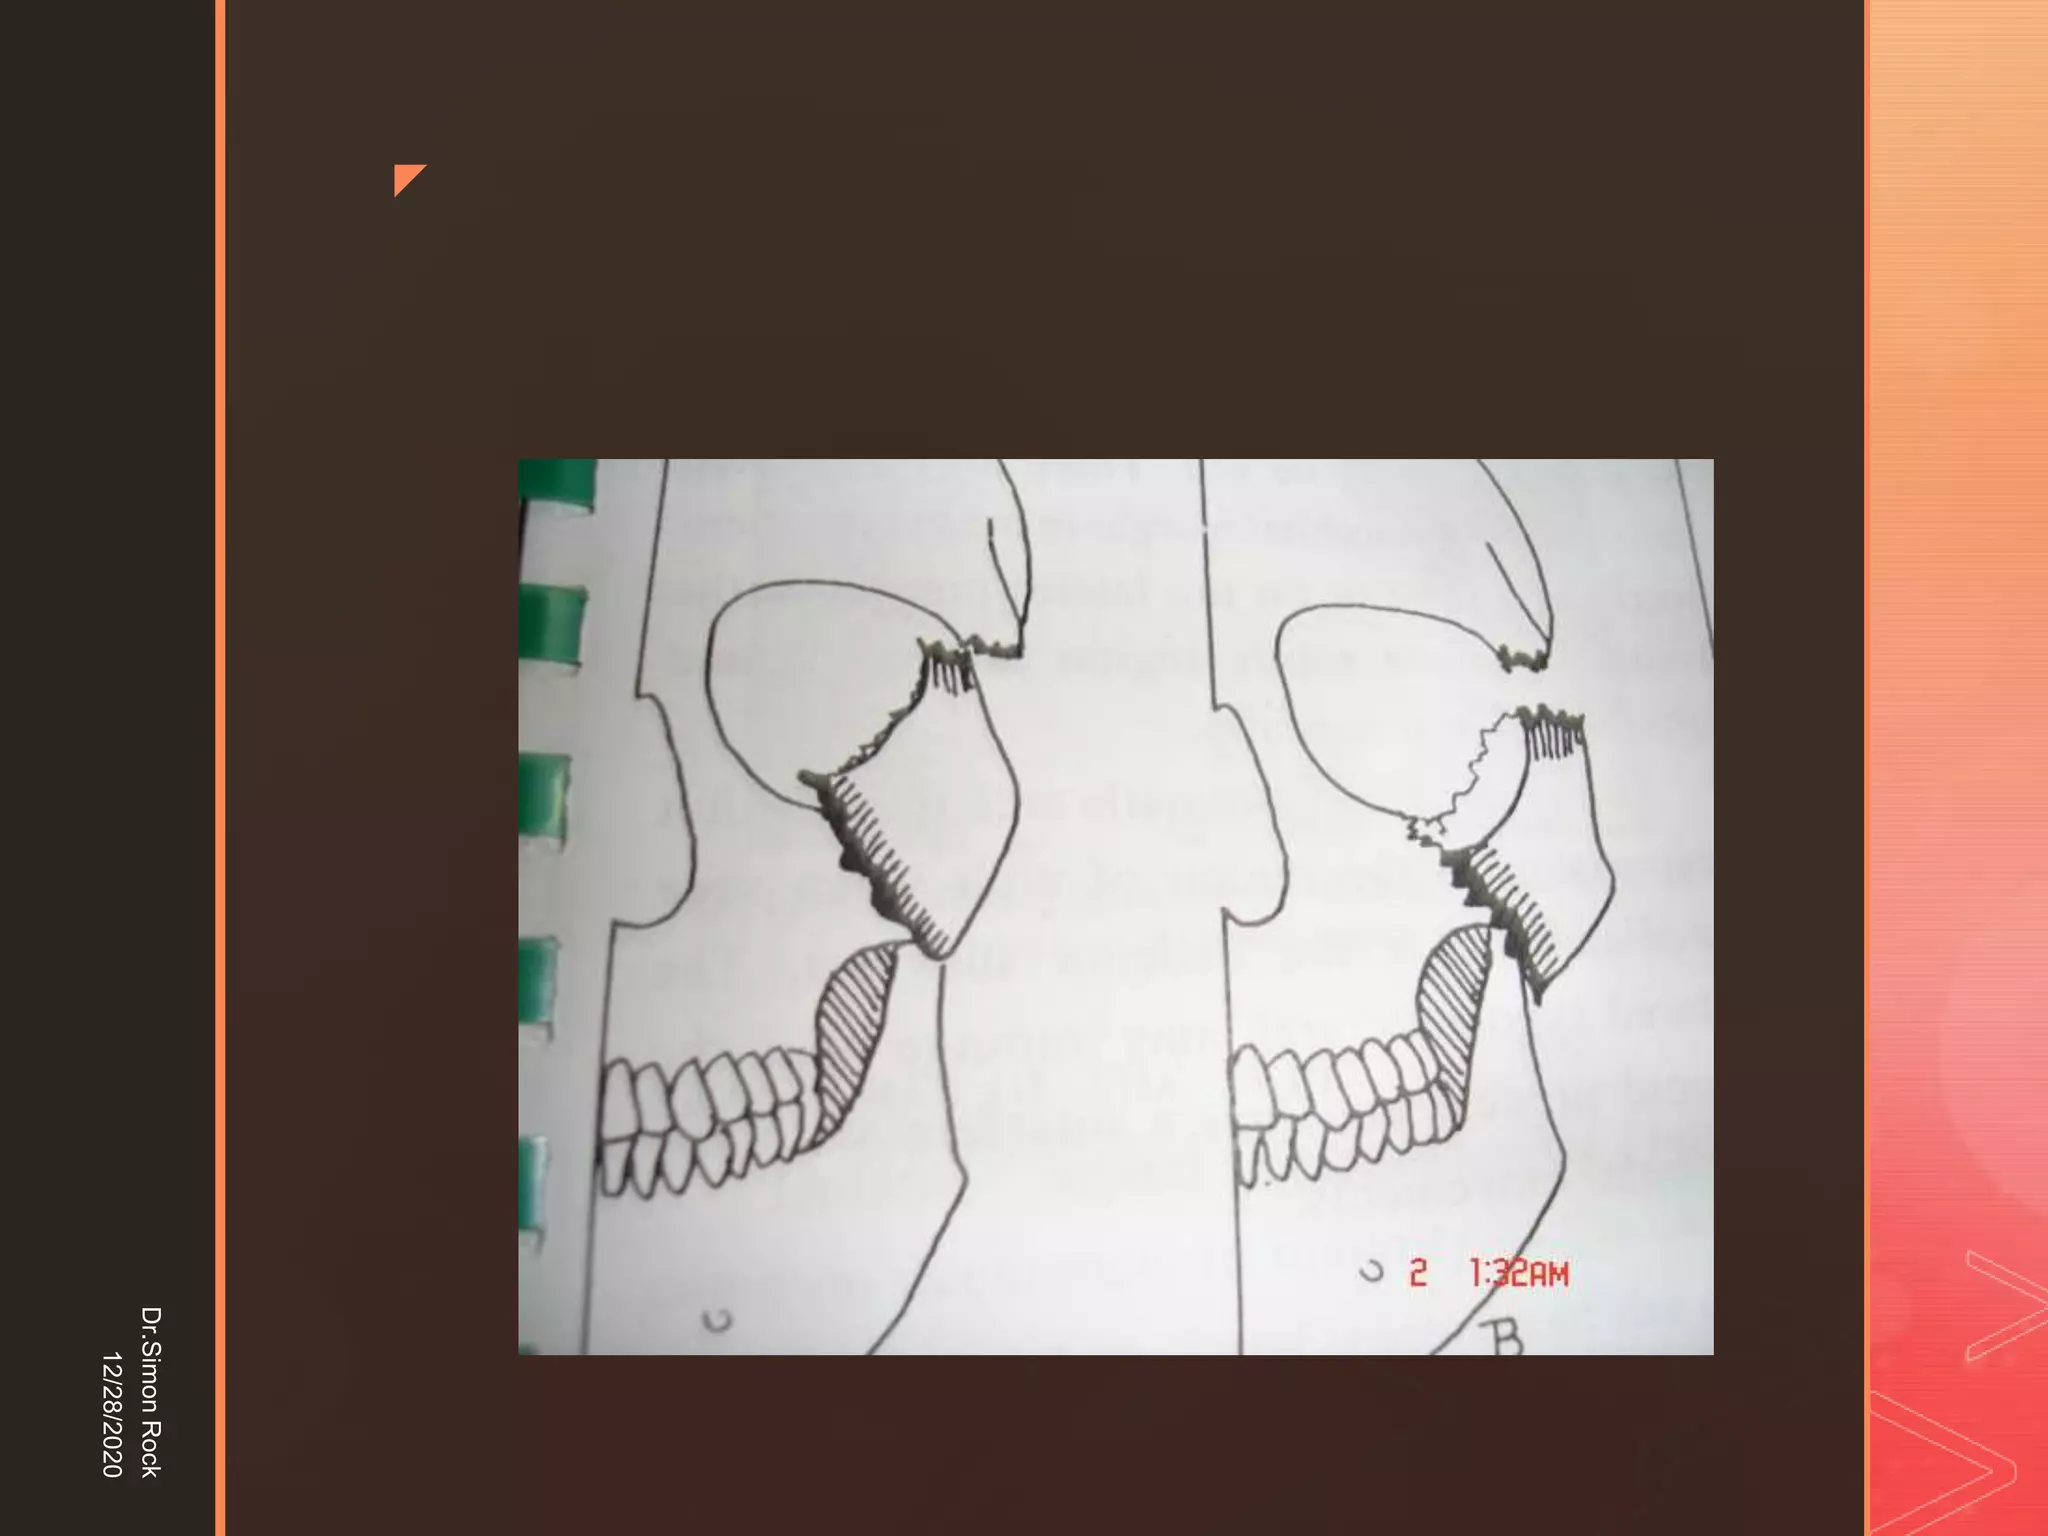

This document discusses the anatomy and fractures of the zygomatic bone. It notes that the zygoma forms the cheekbone and articulates with several other facial bones. Zygomatic fractures most commonly occur in the arch or body due to blunt trauma. Diagnosis involves checking for diplopia, ecchymosis, and other signs of orbital or facial bone involvement. Treatment may involve closed or open reduction based on the severity of displacement. Closed reduction techniques try to elevate the bone back into position without surgery, while open reduction requires surgical exposure and fixation of the fracture site.